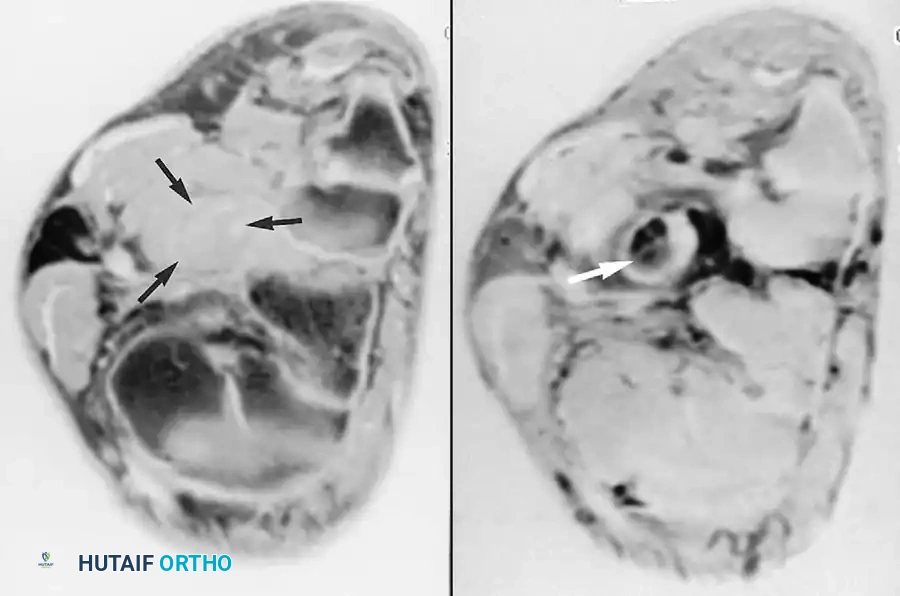

Fig. 2-2 Partial tear of calcaneal tendon. A, Sagittal T1-weighted image shows markedly thickened calcaneal tendon containing areas of intermediate signal. B, Sagittal fat-suppressed, T2-weighted image exhibits fluid within tendon substance, indicating partial tear.